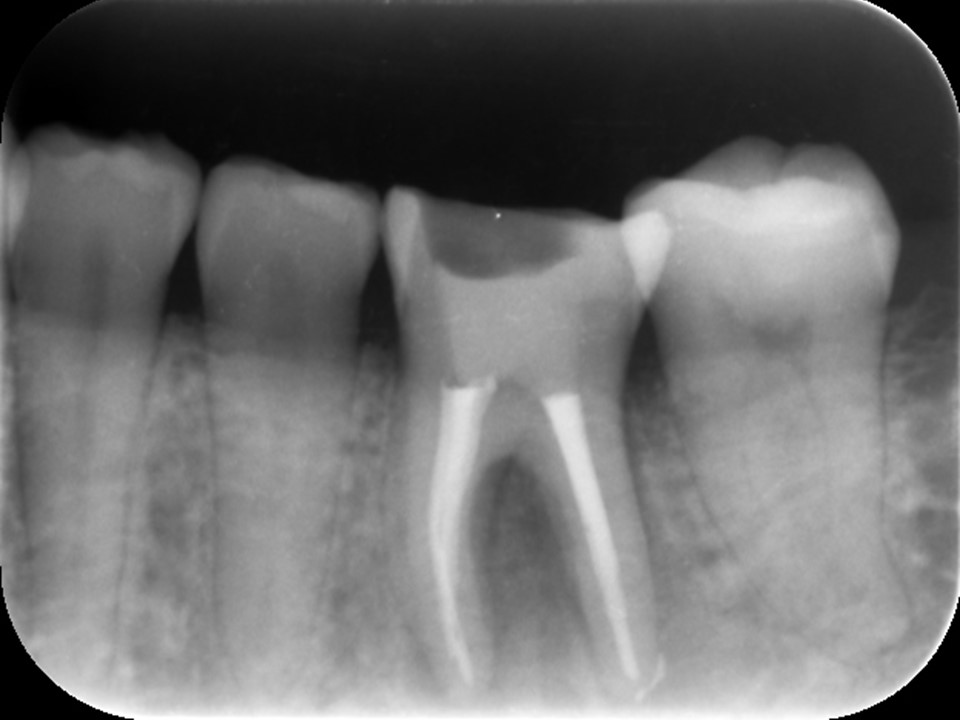

初診時レントゲンおよびCT画像です。根尖部には根尖病変と思われる黒いX線透過像を認めます(矢印)。

歯冠部には、歯髄に近接するレジン充填と思われる白いX線不透過像を認めます。深い虫歯治療後に歯髄壊死を生じたと推察されます。